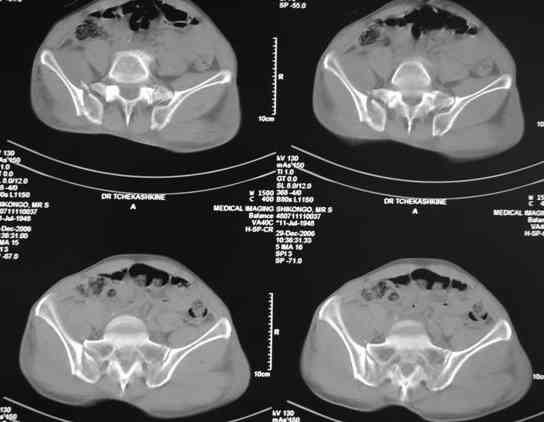

Вчера прооперировал больного.

Попытка низвести половину таза на тракционном столе ( скелетное вытяжение за бедро) безуспешная.

из переднего доступа добрался до правого КП сочленения , все запаяно костью, с помощью 2 шанцев винтов в крестец и подвздошную кость и элеватора репозиция, контроль ЭОП

и двумя пластинами фиксация.

Спереди, аппарат как рекомендовал Джолдас.

Снимки плохого качества( очень темные) завтра переделают и пришлю на конференцию.

На мой взгляд, смещение устранено и фиксация выглядит вполне анатомичной.

В приложении послеоперационные картинки.

Всего доброго,

Спасибо всем принявшим участие в обсуждении,

Чекашкин Е.И.